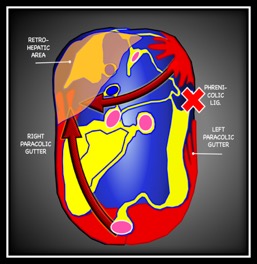

Fluid flows downhill and respects boundaries – it must build up in one area before overflowing to an adjacent area. This seems simple but in the context of the FAST exam it relies on a comfort with somewhat abstract anatomy.

To simplify things, I think of a body lying supine with all of the peritoneal organs removed except for the liver – which must remain as it is tethered to the diaphragm. What you have is the smooth contour of the retroperitoneum and its reflections:

Now we have to consider some other factors, the bladder limits the amount of fluid that can fit in the pelvis so this quickly spills over the pelvic brim.

In order to reach the upper peritoneum fluid from the pelvis must travel along one of the paracolic gutters, the left paracolic gutter is relatively higher than the right and flow is limited by the phrenicolic ligaments so pelvic fluid almost always spreads first to the caudal tip of the liver in the RUQ.

The spleen is the most common source of hemoperitoneum in trauma, and unlike the liver it is small and untethered allowing blood to collect beneath it. This is the reason for emphasizing the ‘6 to 9 o-clock’ view in the LUQ. This is often the first and only place blood can be seen in a serious splenic injury. When explaining this to juniors it can help to reference a coronal slice of a CT. This video shows the superimposition of the US image on the CT. Note how much of this splenic bleed is invisible to the initial view.

It helps understand where the 6-9 o clock position actually is and helps explain why interrogation of this deep recess is so important.